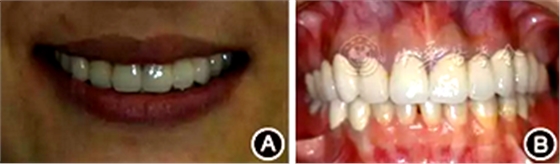

口腔衛(wèi)生狀況一般,菌斑指數(shù)0~2,鄰面少量軟垢;牙齦齦緣鮮紅、水腫、質軟,出血指數(shù)2~3,余牙牙齦輕度水腫,出血指數(shù)0~2;全口探診深度2~3 mm,個別位點探診深度達4~5 mm,鄰面可探及附著喪失;未查及牙齒松動及根分叉病變;烤瓷固定橋修復,冠邊緣密合度欠佳,位于齦下1~2 mm;、唇側崩瓷,邊緣暴露;上前牙牙齦線不協(xié)調(diào);缺失,右下后牙可摘局部義齒修復,固定橋修復;近中面銀汞充填,近中懸突及繼發(fā)齲;上前牙覆蓋下前牙牙冠的1/2~2/3(圖1)。

圖1 患者初診時臨床照片 A:正面微笑像;B:正面口內(nèi)像